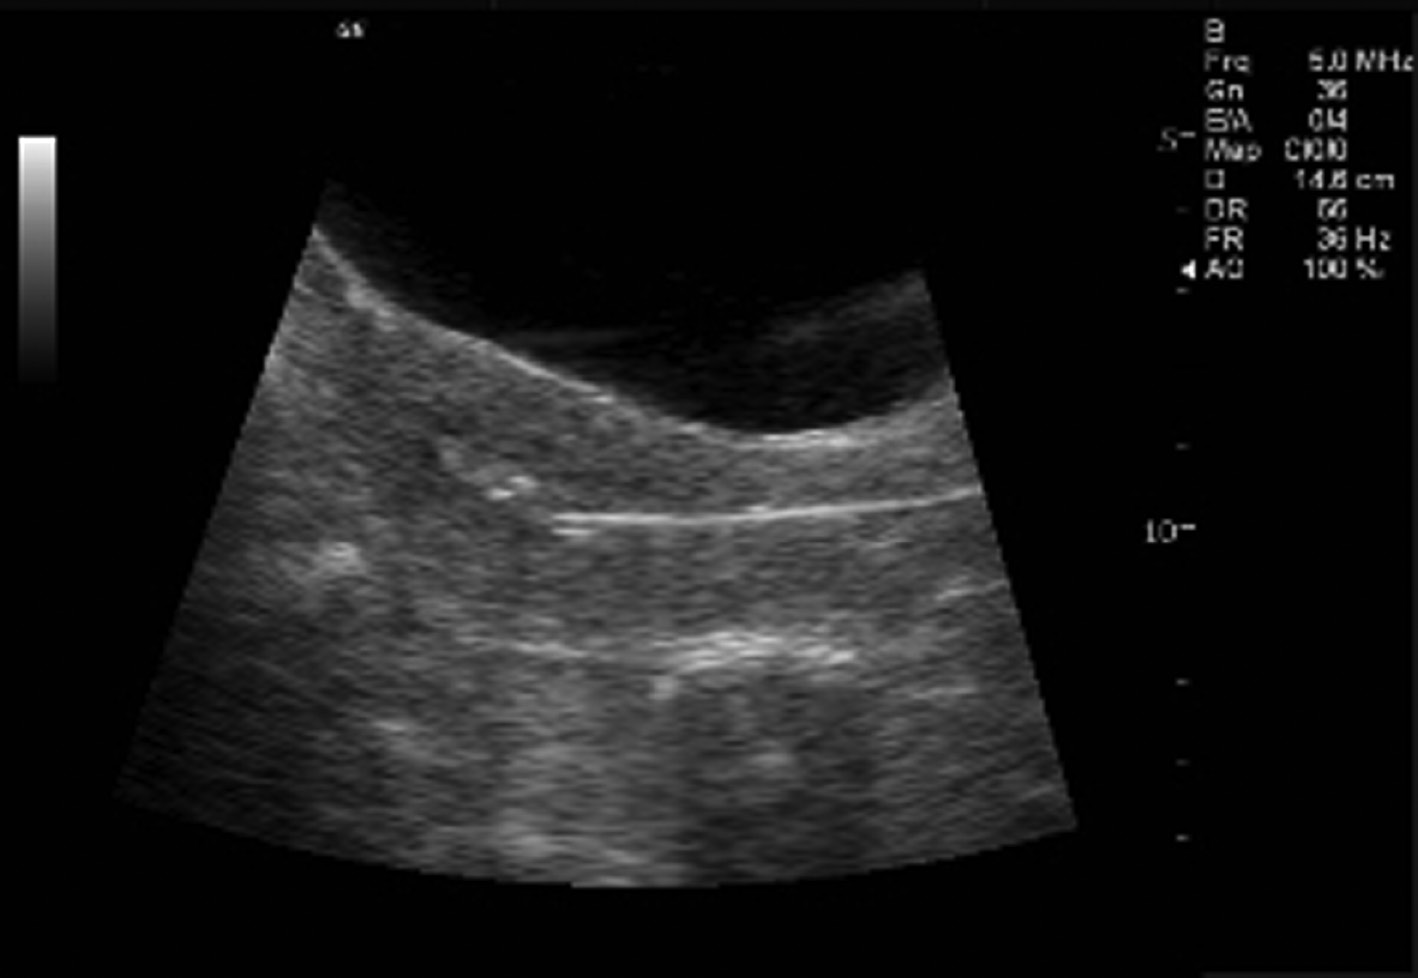

The common first step will be a dating scan between 7-10 weeks as we like to check your baby before 10 weeks . Why scan at 7 weeks? An ultrasound is performed at this stage of pregnancy to confirm your due date, confirm if you are having singles, twins or more and to visualise your baby's heart beating .

We identified 1268 first trimester ultrasound scans done at 6 (+1d) to 9 (+0d) weeks of gestation where gestational age at the day of the ultrasound could be precisely determined using the IVF dates . We calculated IVF dates by noting the number of days from fertilisation until the date of the ultrasound assessment .